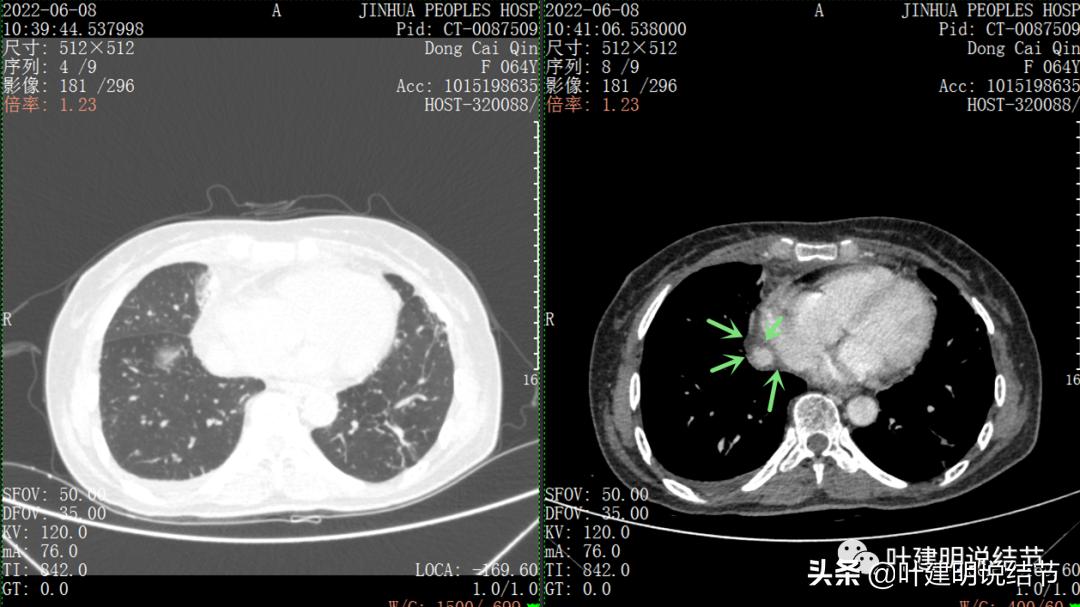

再来看看她的CT增强图像:

以下图片左侧是肺窗,右侧是纵隔窗。红色箭头示病灶,桔色箭头示无名静脉,黄色箭头示支气管,砖色箭头示上腔静脉,蓝色箭头示主动脉,紫色箭头示肺动脉。

绿色箭头示近膈面处,心脏边病灶